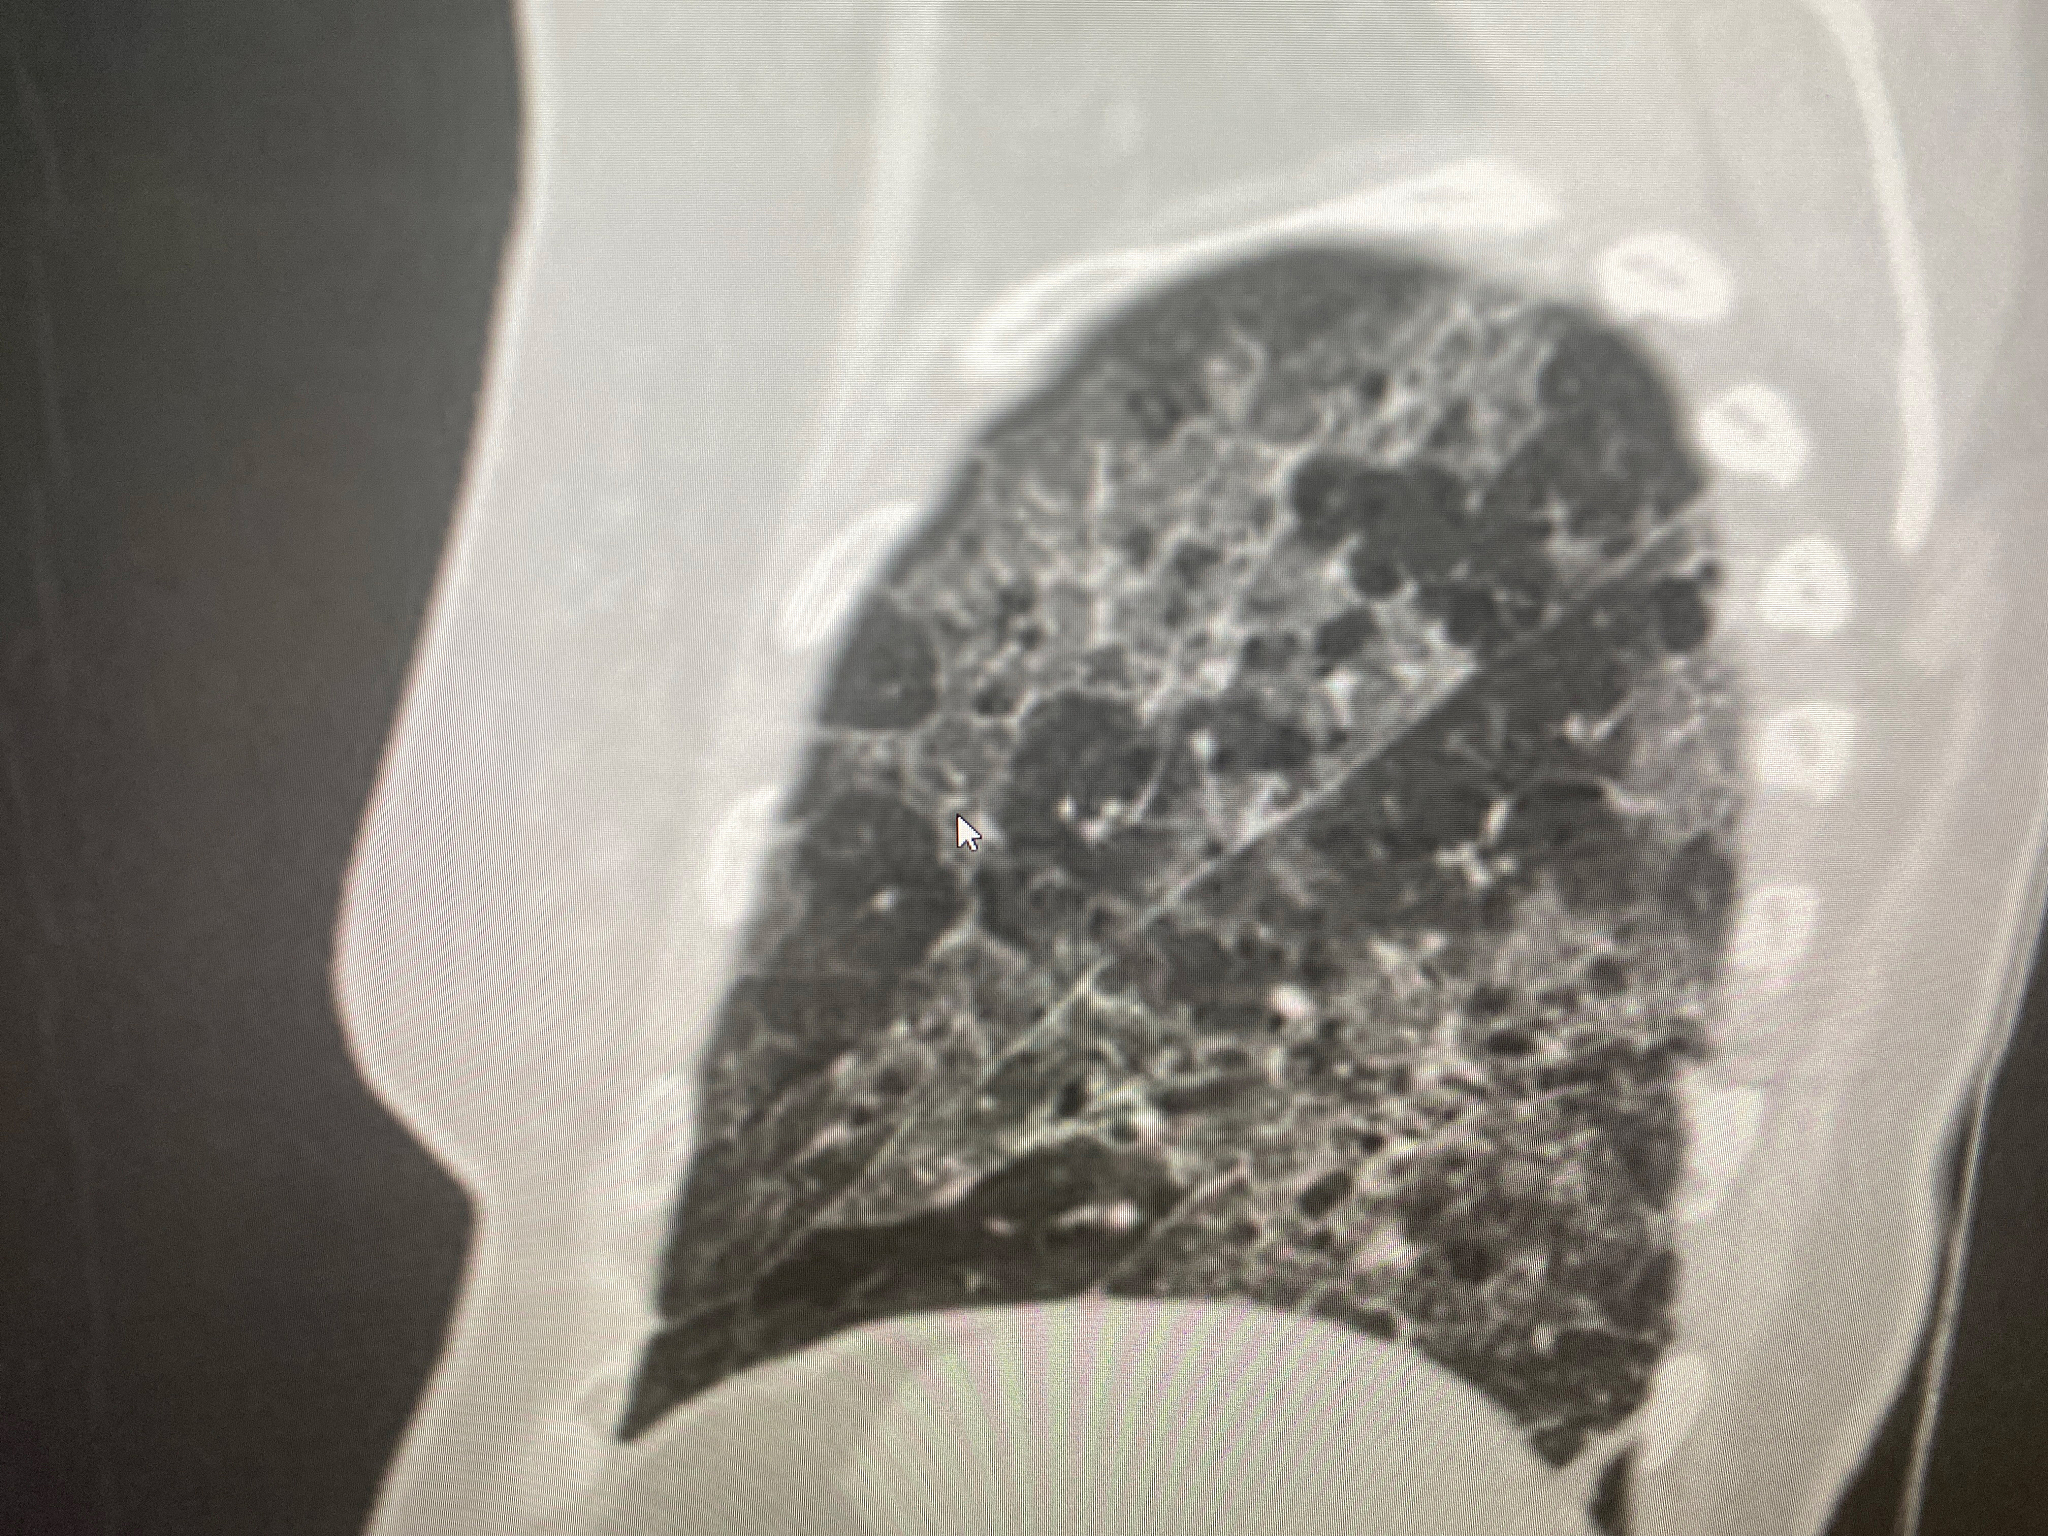

给以下文案写一个标题党的标题现在啊随着薄层CT的普及和大家对于体检的重视发现肺结节的患者越来越多了那什么样的肺结节需要手术呢?简单来说啊就是当怀疑肺部小结节可能是恶性病变的时候就要考虑进行手术了。临床上通过判断肺小结节的大小和密度来区分良恶性。首先让我们来谈谈结节的密度不同密度的肺小结节有不同的恶性概率。根据结节的密度可以将肺结节分为实性结节、部分实性结节和磨玻璃密度结节。其中部分实性结节的恶性概